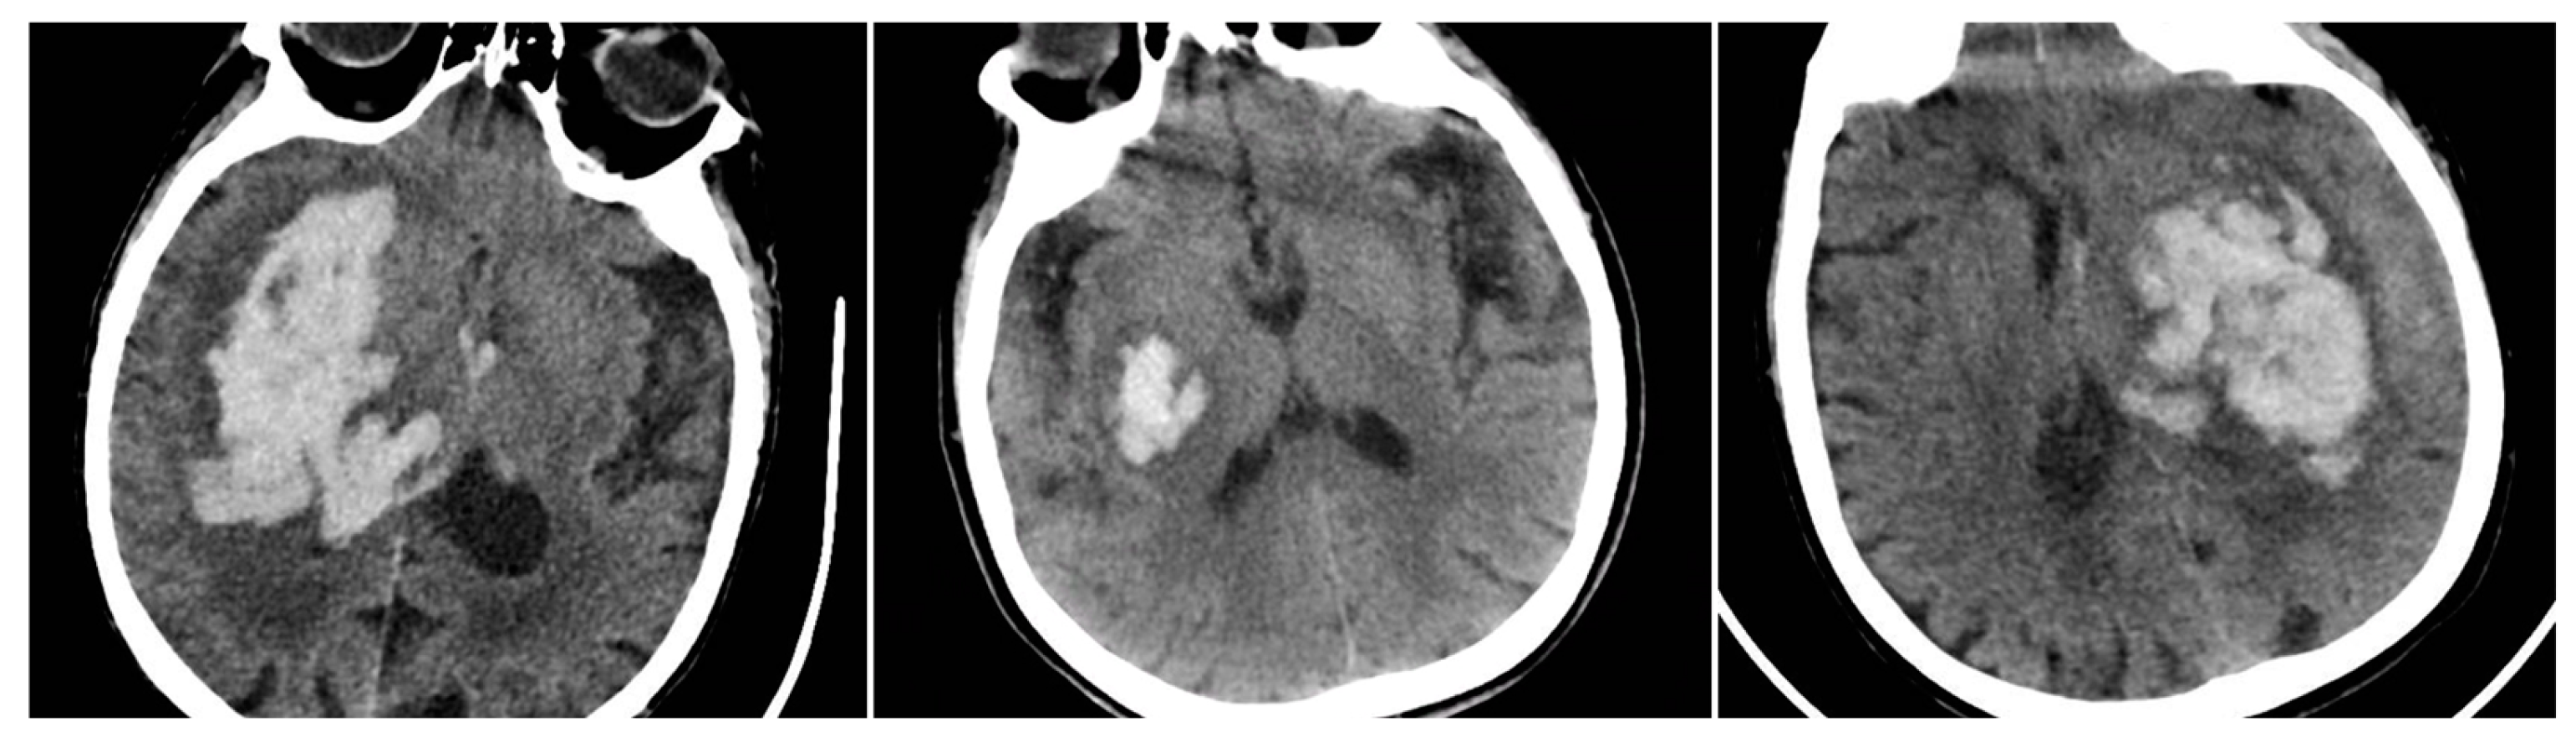

Below is an illustrative breakdown of hematoma expansion according to the presence of each NCCT sign on baseline imaging. In this dataset, 89 out of 404 patients (22.0%) demonstrated significant enlargement (“YES”) on follow-up CT, whereas 315 (78.0%) did not progress (“NO”). Table 2 shows that all four radiological signs were substantially more frequent among those with hematoma expansion. Notably, the Black Hole Sign (BHS) has the most pronounced association with expansion, affecting 56.2% of patients in the “YES” group versus 23.8% among “NO” cases (p<0.001 by chi-square). This observation reinforces the concept that a distinct hypodensity within the main clot may reflect ongoing or repeated hemorrhage, placing the patient at higher risk of volume growth.

Despite these robust associations, several limitations warrant consideration. Early surgical evacuation in some patients may have led to underestimation of expansion, while late presentation could mean that signs such as the Blend Sign reflected a post-expansion state rather than a purely predictive marker. Additionally, “slightly irregular” shapes can be subjective. Overall, however, the Black Hole Sign appears most strongly correlated with hematoma enlargement, underscoring its potential as an indicator of ongoing bleeding risk (Figure 5).

Figure 5. Left: ICH with expansion with the presence of BHS and IRS; Right: ICH without hematoma expansion, no NCCT Signs observed